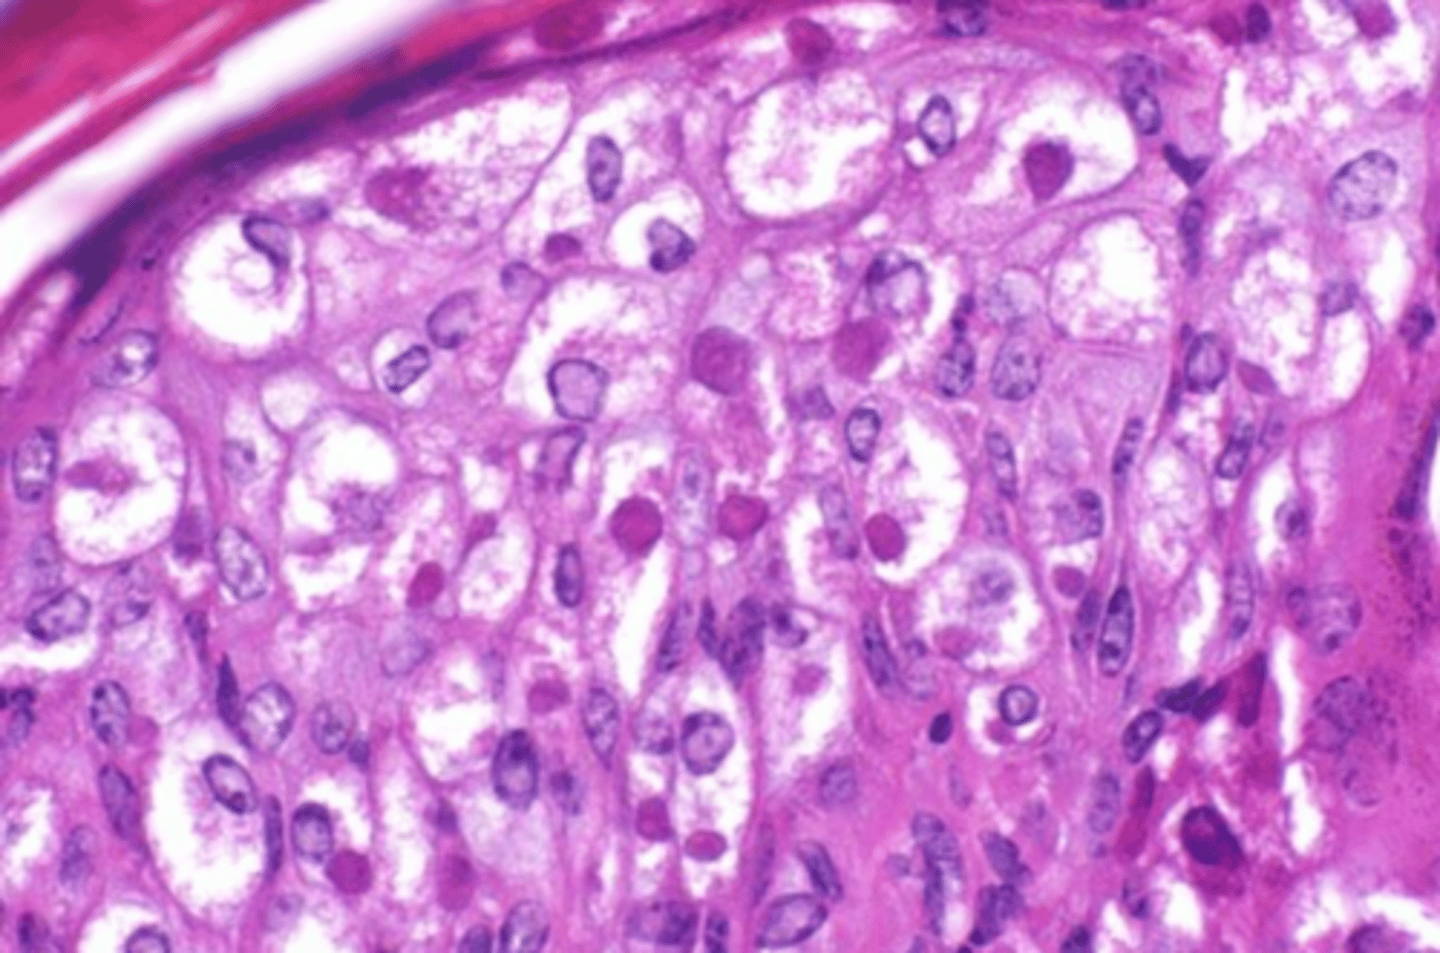

macrovesicular lipidosis

Which type of lipidosis is this describing?

Large, clear, sharply defined vacuoles that are larger than the nucleus, distend the

cytoplasm, and displace the nucleus to the periphery of the cell

macrovesicular hepatic lipidosis

yellow arrow?

microvesicular hepatic lipidosis

blue arrow?

displaced nucleus

blue arrow

macrocytic lipidosis - large cytoplasmic vacuole

yellow circle?